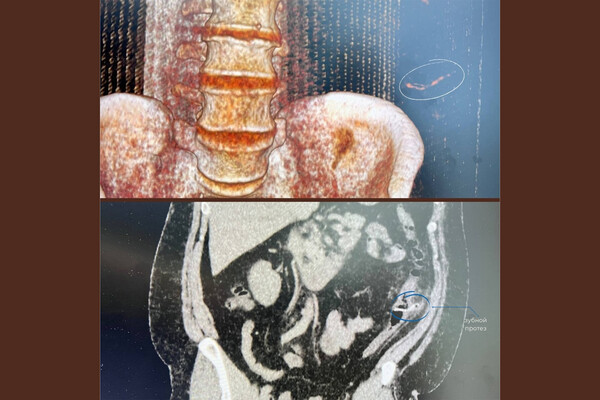

Врачи Нижневартовской окружной клинической больницы помогли пациенту с зубным протезом в кишечнике. Об этом сообщили в пресс-службе медицинского учреждения.

Пациент обратился к врачам с жалобами на боль в кишечнике и повышенную температуру тела. Мужчина рассказал, что за два дня до визита в больницу он случайно проглотил зубной мост.

Обследование показало, что протез из-за своей формы зацепился за стенку кишечника и вызвал воспаление. Не обнаружив у мужчины прободения кишечника, врачи приняли решение об удалении инородного предмета эндоскопическим путем.

«Сначала мы исключили возможную перфорацию кишечника, а затем приступили к операции: завели колоноскоп, осмотрели нужный участок кишки, «дошли» до зубного протеза, накинули на него эндоскопическую петлю и осторожно извлекли», — поделился врач больницы Ахмад Джабборов.

Через шесть дней после операции пациента выписали из стационара.